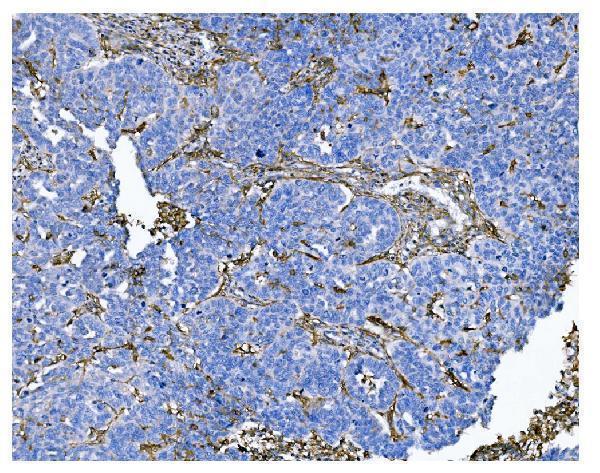

Expressed in epithelial cells of the kidney, intestine, and respiratory tract; granulocytes, monocytes, fibroblasts, endothelial cells, cerebral pericytes at the blood- brain barrier, synaptic membranes of cells in the CNS. Also expressed in endometrial stromal cells, but not in the endometrial glandular cells. Found in the vasculature of tissues that undergo angiogenesis and in malignant gliomas and lymph node metastases from multiple tumor types but not in blood vessels of normal tissues. A soluble form has been found in plasma. It is found to be elevated in plasma and effusions of cancer patients.